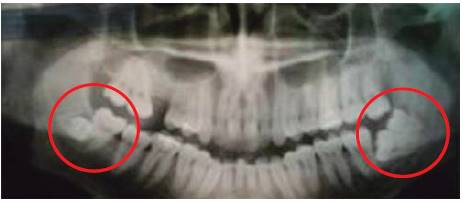

Fourth molars or distomolars, since they not always exhibit isolated symptomatology, are mostly found after X ray examinations conducted to treat third molar problems (Figure 24). Fourth molars are rarely found erupted, thus first findings are clinical.

Figure 25 Presence of lower right fourth molar exerting pressure in the distal root of third molar and presence of left lower fourth molar, both compromising the vascular-nervous package.54